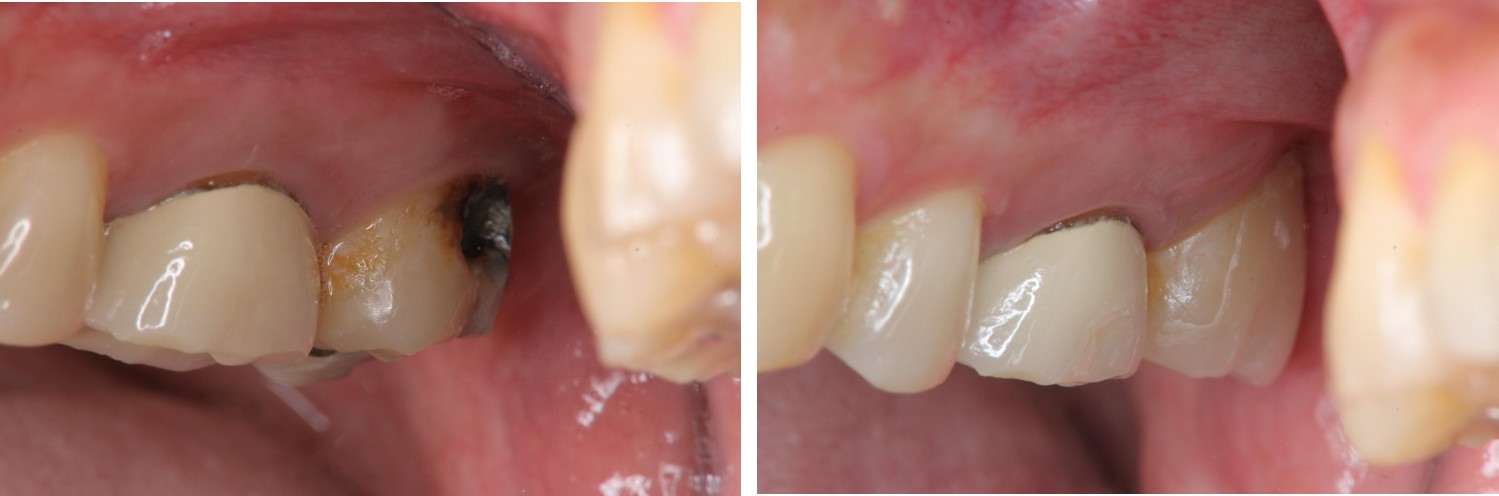

治療前,頰側牙齒蛀牙

治療後口內照

術前、術後比較